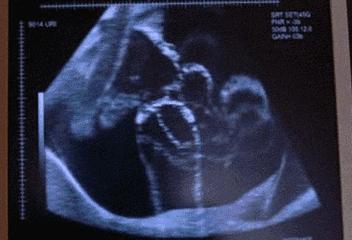

乐乐哭声嘹亮,但两条小腿,从膝盖到脚背和趾头的部位, 就像被削了一层皮一样,

血红色的肌肉暴露在外,就连血管脉络都清晰无比 ,甚至轻轻一碰,就会 破裂、流血! 随时面临着感染的风险。

经过进一步检查,大伙才知道乐乐是 先天性皮肤发育不全。

这是一个发病率非常低的病症,大约十万分之一,目前,国内能查到的相关报道只有258例!

他只是没有表皮和真皮,但皮下组织和肌肉还完好无损。

而且,他缺少的皮肤面积不算太大, 占体表面积的9.7%。